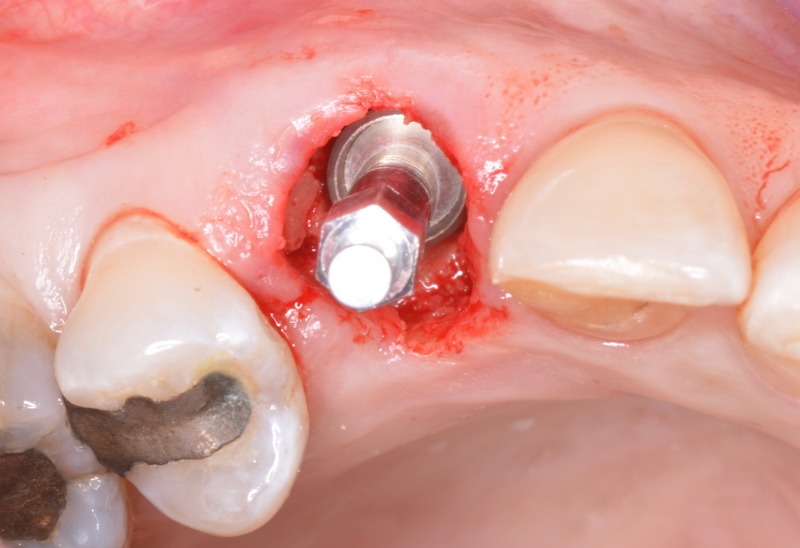

Immediate implant placement for tooth #13 after extraction. It was followed by immediate provisionalisation. (Image: Barry P. Levin)

What are the main learning objectives for the viewers of your webinar? Viewers will learn the value of recording ITV and ISQ measurements at the time of implant placement and how to apply these values with regard to loading protocols. I will also discuss possible negative effects on crestal bone if an excessively high ITV is required to fully seat an implant in healed or grafted sites. In addition, I will highlight the importance of recording ISQ values not only at the time of implant placement but also at follow-up periods to monitor and confirm secondary stability.